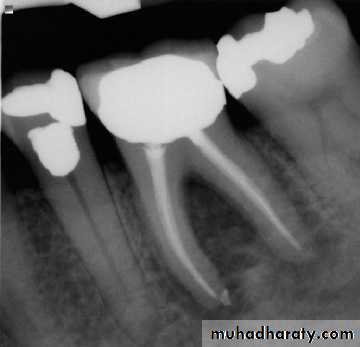

Radiograph of occlusal caries. This radiograph shows (1) severe occlusal caries, which appears as a large radiolucent lesion in the first molar